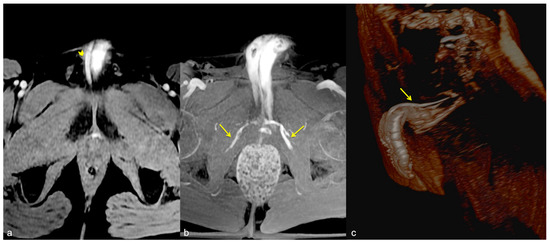

Figure 7.

Cav-MRI. The axial (a) and coronal (b) GRE T1W 3D FS images after contrast agent injection, displayed with MIP reconstruction, show an early opacification of the crural veins ((a), arrows) and of the obturator veins ((b), arrows), supported by venous leakage mediated by the deep dorsal vein of the penis ((b), arrowhead).